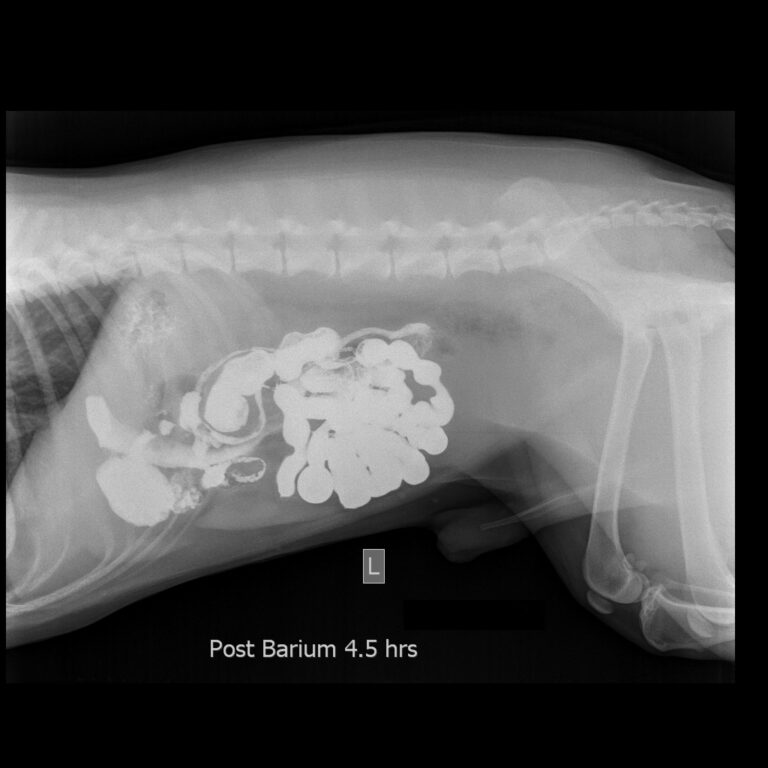

contrast-x-ray-dog

Contrast X-ray

The body’s soft tissues do not absorb x rays well and can be difficult to see using this technology alone. Specialized x ray techniques, called contrast procedures, are used to help provide more detailed images of body organs.

In these procedures the animal is given a dye that will block x rays. This can be given intravenously to examine organs like the kidneys or heart, or by mouth to examine the digestive tract. A series of x-rays is taken after the dye is given, which will outline the organs where the dye collects. This makes it easier to spot any abnormalities.

The x-ray machine is positioned so that x-rays are focused on the area to be examined. Exposure to x-rays lasts only a fraction of a second. However, the greater the exposure, the greater the risk that radiation may damage cells. For this reason, a very low dose is used, and lead shields may be used to protect areas that are not being x-rayed and the people taking the radiograph.

These images are stored digitally on computers to be shared with specialists, other clinics or the pet owners themselves.